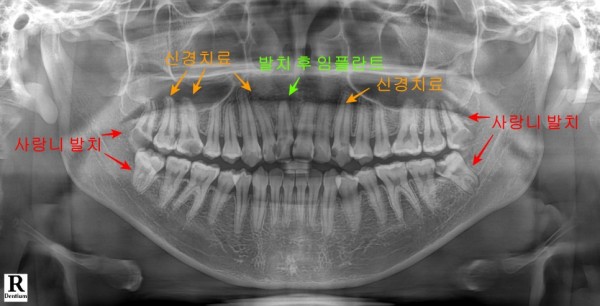

구강 검진 결과, 예상보다 상황이 심각했습니다.

오랜 기간 방치로 인해 전체적으로 충치가 상당히 진행된 상태였습니다.

특히 치열이 불규칙하게 배열되어 있어 칫솔질이 어려운 부위에

집중적으로 우식이 발생한 것으로 보였습니다.

상악 좌측 제1대구치(#16)에는 기존에 인레이 치료를 받으셨던

부위 아래쪽으로 2차 우식이 진행되어 인레이가 탈락된 상황이었고,

앞니 부분에도 상당한 우식이 관찰되었습니다.

전반적으로 여러 치아에 걸쳐 치료가 필요한 상태였죠.

상하악 모든 사랑니 발치,

심하게 손상된 앞니는 발치 후 임플란트로 대체,

그리고 신경 치료가 필요한 여러 치아들에 대해서는

지르코니아 크라운으로 수복하기로 계획했습니다.